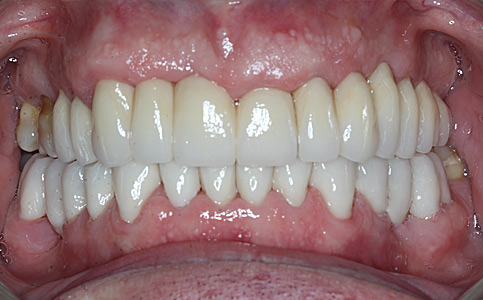

Przykład pełnej rehabilitacji protetycznej obejmujący leczenie biologiczne, uzupełnienie braków zębowych implantami oraz korony pełnoceramiczne w łuku górnym i dolnym. Spektakularna metamorfoza uśmiechu wykonana przez zespół Centrum Stomatologii i Ortodoncji FRESHmed odmieniła życie Pacjenta dodała pewności siebie i sprawiła, że z chęcią się uśmiecha.